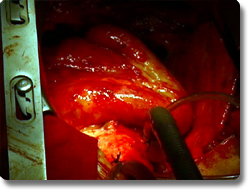

我科共开展500多例3岁以下婴幼儿先心病心内直视手术,最小年龄出生12小时,最小体重3公斤,技术水平达国内先进水平。手术成功率97%,特别是开展的新生儿(3天)完全性大动脉转位矫治术、出生12小时新生儿左全肺萎缩的巨大膈疝修补术、胸腹联体婴儿分离术达国内一流水平。我科开展的法乐氏四联症、完全肺静脉异位引流、房室管畸形、右室双出口、大动脉转位、三尖瓣闭锁、单心房、完全肺静脉异位引流等复杂畸形的心脏手术在重庆市和西南地区领先。